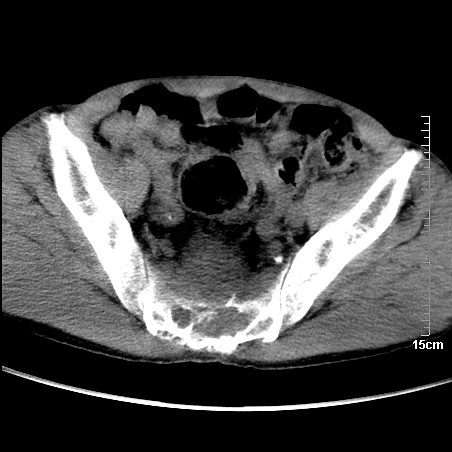

标题: CT16886:骶尾部占位:1.脊索瘤?2.巨细胞瘤?

增强:

1、骶尾部巨大软组织肿块,部分骶尾骨以被软组织肿块代替,呈不规则侵蚀;病变突向盆腔内;增强扫描病变呈不均质强化;首先考虑脊索瘤。不支持的一点就是病变内无钙化。

2、发生于骶尾椎者须与骨巨细胞瘤鉴别,骨巨细胞瘤一般发在上疗骶椎,肿瘤内无钙化,一般无侵袭性生长的表现。